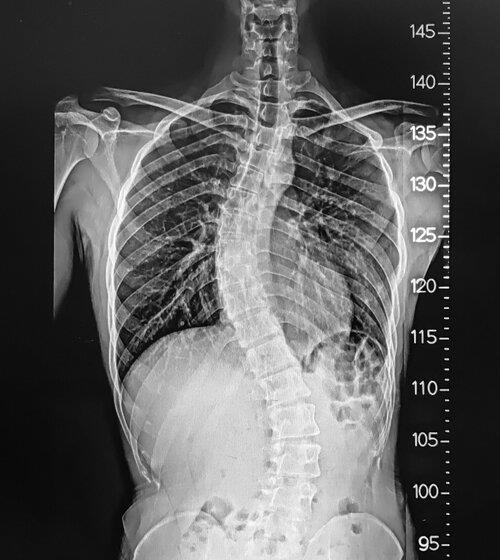

While increasing age, many people suffer from spine issues. At the right time, people can take the right cure from the Spine Surgeon in Sun City West after fixing an appointment in the Banner Health Clinic. He knows how to reduce spine pain from the root using the latest microinvasive technique. While performing the robotic spine surgery, Dr. Andrew Chung gives his 100% effort to safely remove the damaged disc herniation, nerves, or infected tissues. To learn more, click on the link.

With the latest micro-invasive technique, Dr. Andrew Chung removed the damaged Disc Herniation in Phoenix. At Banner Health Clinic's outpatient setting, he successfully performed many spine surgeries, including robotic. Before giving the proper non-surgical or surgical treatment to the patients, he finds the spine health problem through the medical test reports. Here in the clinic, he is the only surgeon who is an expert in treating back, neck, arm, and other spine-related injuries. For an appointment, click on the website.

Back fusion Phoenix/Back Surgeon Phoenix